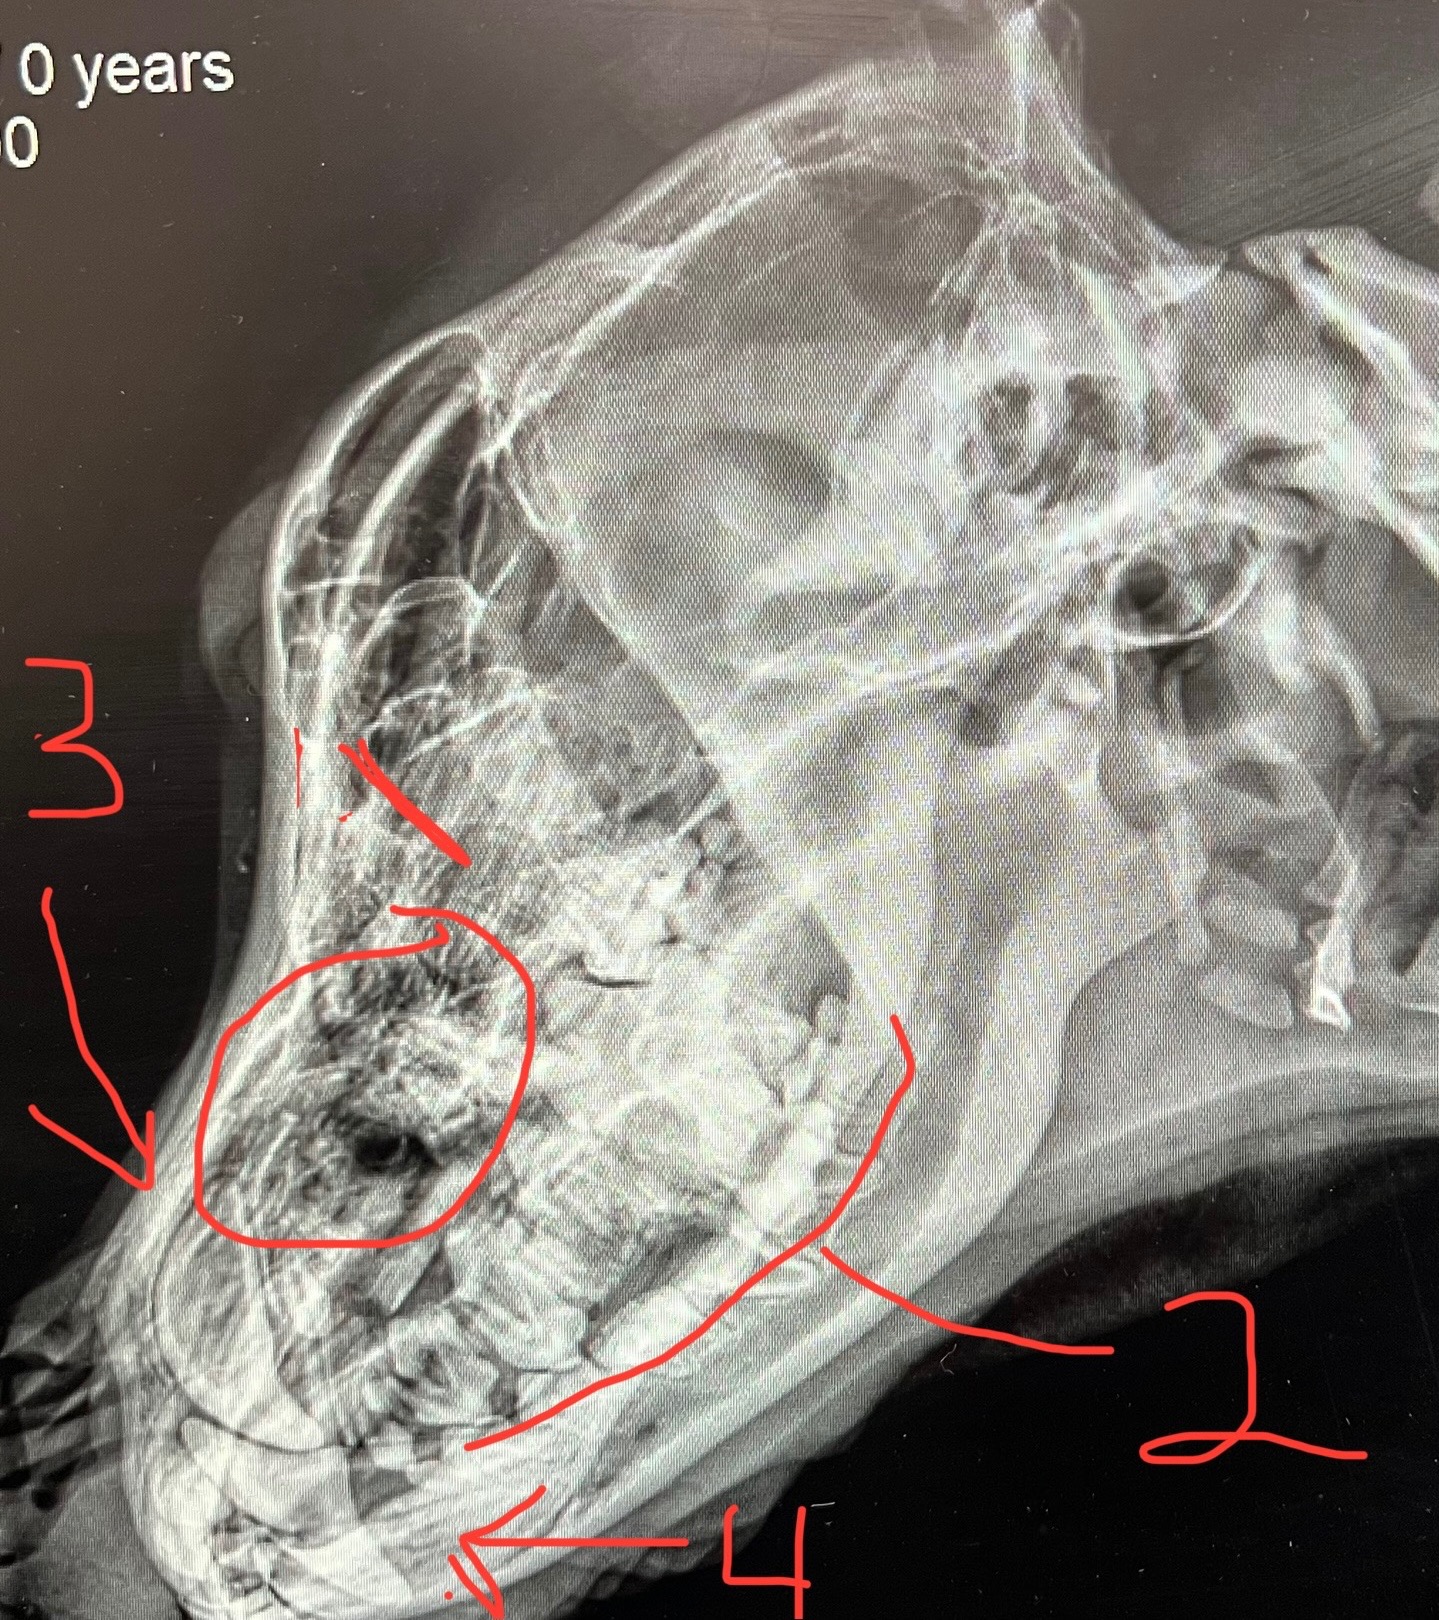

took us 2 a place where they looked nside my mouth N said a bullet went thru the top N left 3 BIG holes.

Buster’s 1st surgery is scheduled for May 29 and the 2nd surgery is now scheduled for July 14 at Texas A&M University. They have a high-tech facility where they are able to perform a surgery of this kind, that entails the reconstruction of the inside upper part of his mouth where the bullet passed through. The pallet bone in the middle of his mouth was shattered, along with several teeth. Three gaping holes were left in the top of his mouth from the bullet and half of his tongue was severed. Bone fragments were removed and his tongue was stitched. There are areas where the skin has grown back inside his mouth, but it is still hollow underneath the skin, which could be punctured at any time. They will need to construct a mesh that will emulate the actual pallet bone that we all have in the top of our mouth, so the skin can grow over that and enclose the hole along with enforcing bone where teeth were shattered.

The dental surgeons at Texas A&M have said without the surgery and closing the holes, which are slightly open to his nasal passages, that his life would always be at risk because even if he is being carefully hand fed and given water through a syringe, there is the risk of some of it ending up in the hole of his nasal passages and going to his lungs which would cause him to aspirate and result in a painful death.